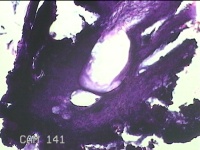

3、7、11点肿物

性别

男

年龄

34岁

临床诊断

1.混合痔 2.肛裂

一般病史

大便出血半年,伴粘液便。

标本名称

大体所见

灰白暗红色肿物1.8x1x0.3cm两个,表面糜烂。

痔是有的。